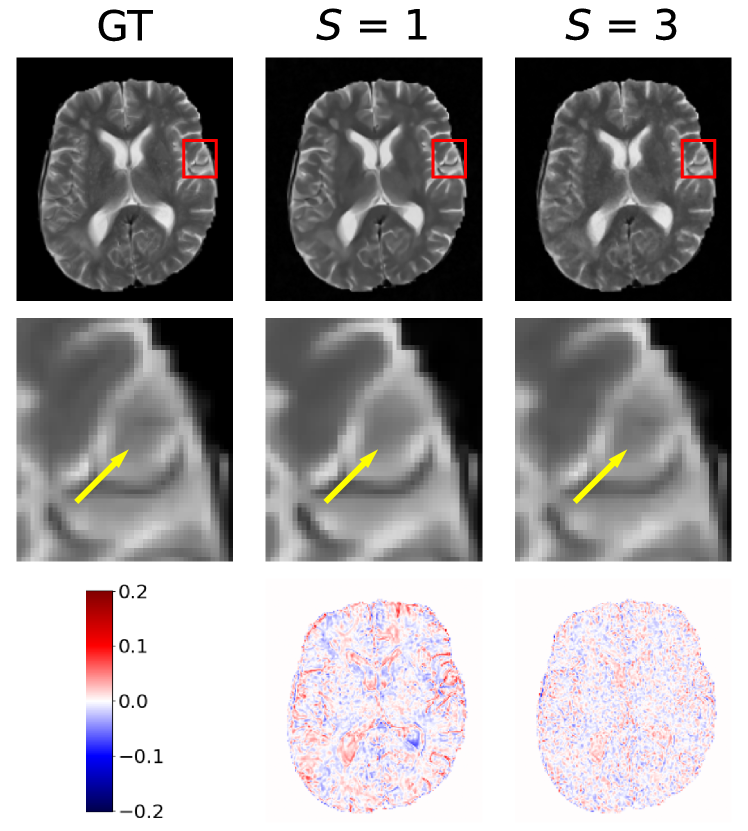

Furthermore, selected reconstruction results are visualised in Fig. 2. The reconstructed images and corresponding error maps demonstrate the capability of our proposed method in capturing finer anatomical details, and it is consistent across both contrasts and all evaluated acceleration rates, indicating the superiority of our algorithm in reconstructing high-quality MR images from sparsely sampled -space data.

The reconstruction images for 3D data are displayed in Fig. 3. For comparison purposes, the same slices selected for the 2D data evaluation are extracted. Even with sparsely under-sampled data, our proposed method demonstrates precision in reconstructing whole-brain volumes, successfully capturing detailed structures that other methods struggle to reproduce. This visual representation, combined with the quantitative data, indicates the superior performance of our proposed reconstruction method in a 3D context.

The reconstructed slices displayed in Fig.2 and Fig.3 visually confirms these findings. The 2D representation typically yields reconstructions of higher quality, capturing finer details more effectively. On the other hand, direct reconstructions from 3D volumes tend to appear less sharp or accurate. This observation reflects the trade-offs between data complexity, model performance, and operational efficiency in MRI reconstruction of different data representations.